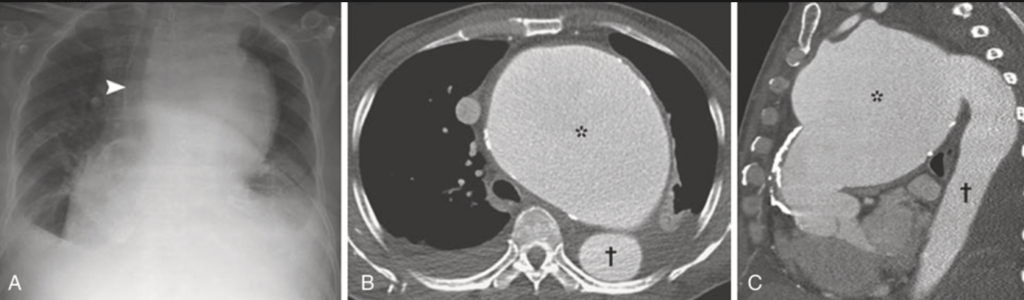

① 近位大動脈の拡張、上行大動脈の前外側壁の線状石灰化(古典的なXp所見)

動脈瘤は50%は上行大動脈弓に生じ、巨大化しても症状に乏しいため”aneurysm of sings”と呼ばれる。ついで30-40%は横行弓に生じ、縦隔内の構造物に隣接するため”aneurysm of symptoms”と呼ばれる。